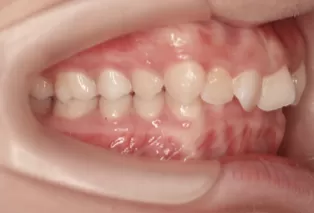

Intraoral photos